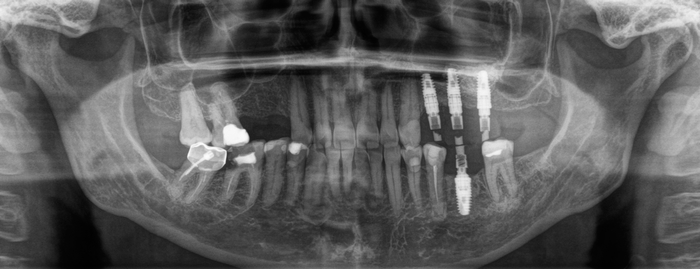

Бонусом еще небольшой клинический случай, как можно передвигать зубы на свое место:

Был установлен имплантат, и параллельно начато лечение у ортодонта. Как мы видим, нижний правый седьмой зуб наклонен, а верхний правый шестой несколько выдвинулся в сторону отсутствующего шестого на нижней челюсти.

Обратите внимание: необязательно устанавливать полноценную брекет-систему для того, чтобы устранить эту проблему. Достаточно приклеить 3 брекета на 4-й, 5-й и 7-ой зубы. Затем при помощи специальной пружины толкать проблемный зуб на свое место. На верхней челюсти ситуация несколько иная. Для устранения проблемы устанавливаются два ортодонтических винта: один со стороны щеки, а второй со стороны неба. К зубам клеятся две кнопки, и дается тяга.

И под другим углом: